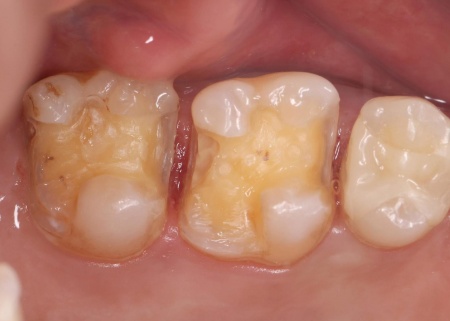

| 診断 | 患者様には、まず皮膚科での金属アレルギー検査をおすすめしたところ、歯科治療で使用していた金属がアレルギーの原因と判明しました。 患者様の口腔内には、金属素材で修復が行われている部位があり、これが体調不良につながっていたと考えられます。 以上のことから、口腔内の金属をすべて除去し、金属を使わない材料で修復する必要があると診断しました。 |

| 行ったご提案・治療内容 | 患者様は噛む力が非常に強く、その影響でエナメル質が割れてしまっています。 そこで詰め物の素材には、自費診療の白い素材「セラミック」の中でも、人工ダイヤモンドと呼ばれるほど強度があり、審美性にも優れている「ジルコニア」を選択しました。 すべての詰め物にジルコニアを用いるのが理想でしたが、ジルコニアは費用が高額です。 詰め物の形状には、歯の溝や一部を補う小さな詰め物「インレー」と、歯の噛む面を広範囲で覆う「アンレー」があります。 まずはメタルインレーをすべて外し、詰め物を装着するために歯の形を整え、型取りを行います。 |

治療中